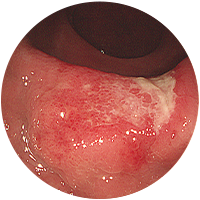

-

3

대장궤양